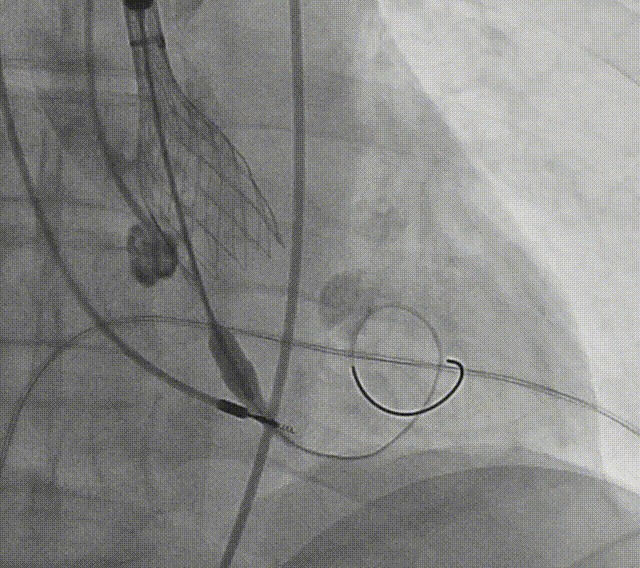

患者病史 术前超声提示:主动脉瓣退行性病变;中-重度狭窄并轻度返流;中-重度三尖瓣返流;中度肺高压 术前CT 三叶瓣,瓣叶增厚轻度钙化,右无交界有粘连,预计可以扩开,主动脉根部直径23.7mm,LVOT直径24.3mm,呈直筒型;双侧冠脉开口高度可,瓣叶长度小于冠脉开口上缘到主动脉根部的距离;窦部空间可,STJ、升主动脉内径可;主动脉水平夹角43.6°,非横位心;主动脉弓角、弓距可,左室内径可;外周入路无明显迂曲,有零星散状钙化,双侧股动脉内径可,均能通过20F大鞘,右股低分叉。 手术策略 推荐右侧股动脉为主入路使用20F大鞘,左侧股动脉为辅入路,右股分叉上方1cm穿刺;推荐使用22mm球囊预扩,预装AV26瓣膜,备AV29瓣膜,初始定位为真实瓣环上方3mm,瓣膜释放过程中释放张力使其自然下滑,工作位观察瓣膜稳定性,最终理想位置为零位;左右重合位:RAO23°CAU32°;右窦居中位:LAO5°CAU12°;左冠切线位:LAO34°CRA14°。 手术过程 术中右股动脉痉挛,内径变为3.8mm,遂更换左腋动脉入路;18球囊预扩,后植入AV26 ProStyle A®瓣膜;瓣膜精准释放于目标位置,超声显示无明显瓣周漏,血流动力学即刻改善。 术中右股动脉痉挛,内径变为3.8mm,更换左腋动脉 主动脉根部造影 18球囊预扩 初始定位 工作位观察 术后即刻表现:无瓣周漏,术后峰值压差10mmHg 术后3天复查超声峰值压差14mmHg Prostyle A®预装干瓣——助力临床最优化解决方案: 轻松过弓,精准可控:该病例经左腋动脉入路,输送系统较细的尺寸+柔顺的输送系统通过性能得到了很好的验证; 释放稳定:平衡的径向支撑力降低了释放过程中的张力,流入端小锥角设计能够迅速锚定贴边,80%可回收使得观察位和释放后的位置差距减少,大大提高了释放过程中的精准性,能够轻松应对高难度病例; 预装干瓣 便捷顺安:金仕生物专利抗钙化技术运用纳米技术去除组织内的细胞碎片和磷脂,封闭游离醛基,从根本上阻断了瓣膜钙化的多项因素,显著提升了瓣膜的耐久性;同时,相比较传统戊二醛保存方式,干式存储最大限度的保留心包的亲水亲油平衡,还原组织天然曲柔性,进一步保障了瓣叶开合,保证长期耐久性; 谢年谨教授 广东省人民医院 谢年谨教授指出:“对于外周血管条件较差的心脏瓣膜病患者,腋动脉路径凭借其更直接的解剖通路与更稳定的输送环境,为手术安全提供了重要保障,尤其适用于股动脉入路失败的复杂病例。该路径不仅能显著降低血管损伤、出血等并发症风险,还能通过更清晰的操作视野提升手术成功率;尤其在高龄、动脉硬化严重的患者群体中,腋动脉路径的适应性优势更为突出。 专家简介 荆志成 广东省人民医院 谢年谨 广东省人民医院 刘勇 广东省人民医院 · END ·